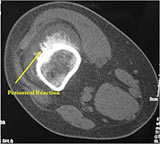

CT Scan:

- Periosteal reaction evident and mass on surface of bone

- May demonstrate subtle mineralization in tumor